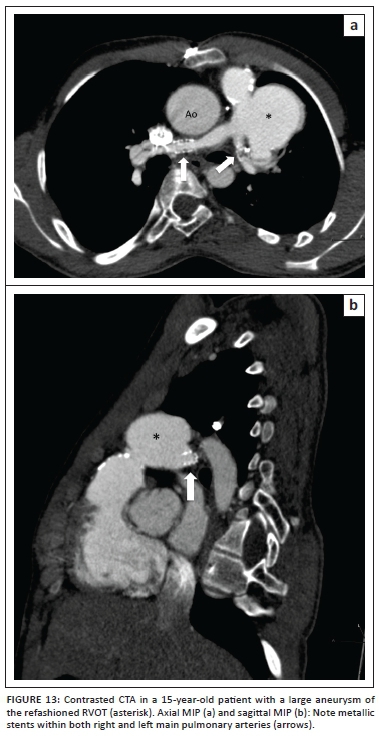

Brock procedure, RVOT and pulmonary artery stents

The effectiveness of the Brock procedure (RVOT relief without VSD closure) can also be effectively demonstrated via CTA. The Brock procedure is performed when the McGoon index is unfavourable and does not allow closure of the VSD at the time of RVOT relief. Pulmonary artery and RVOT stent patency and its related complications (Figure 13) are well documented at CTA and obviate the need for repeat angiography.

Pulmonary outflow tract aneurysm

When the RVOT stenosis is more severe or involves the pulmonary valve annulus, a trans-annular patch repair, using treated pericardium or synthetic material to approximate the margins of the incision, is performed. The trans-annular anterior approach is associated with a variable amount of pulmonary valve insufficiency, resulting in eventual long-term RV dysfunction when excessive. Residual RVOT stenosis is implicated in the pathogenesis of the well-documented post repair complication of RVOT aneurysm (Figures 13-14). The ventriculotomy aneurysm may be complicated by the rare formation of intraluminal thrombus.16